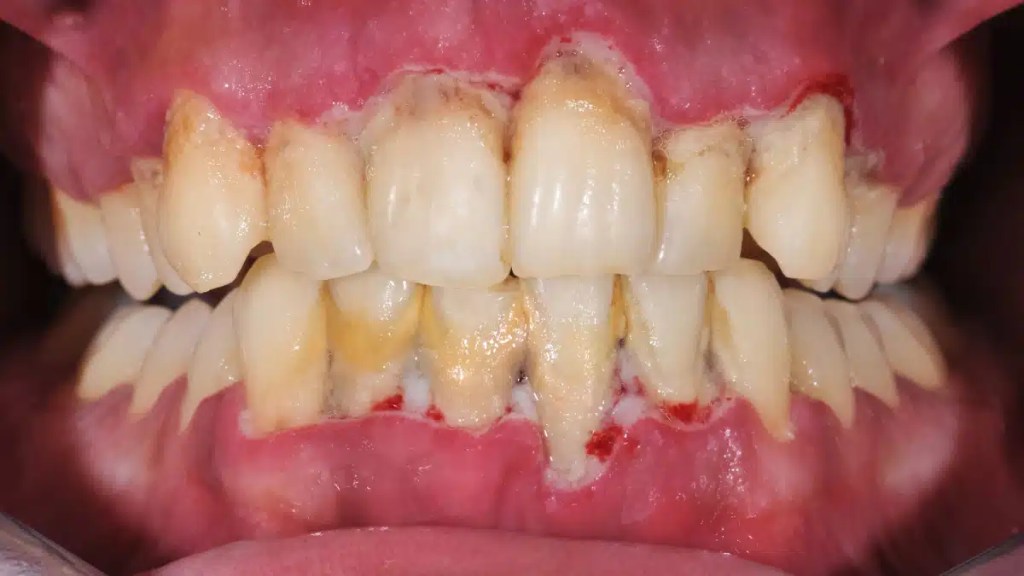

Gengivite

A gengivite é uma inflamação das gengivas causada pelo acúmulo de placa bacteriana.

Quando a imunidade está baixa, o organismo tem dificuldade em combater as bactérias presentes na boca, aumentando o risco de inflamação.

Periodontite

Se não tratada, a gengivite pode evoluir para periodontite, uma infecção mais grave que afeta os tecidos de suporte dos dentes.

A baixa imunidade facilita a progressão da doença, podendo levar à perda dentária.